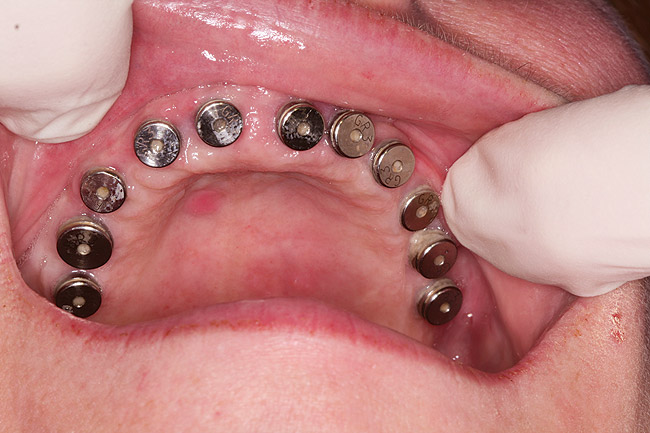

Figure 22  Clinical view of implant uncovering with healing caps.

Figure 22

After 6 months of healing, a CBCT scan was taken and good bone formation was seen on the axial (Figure 18) and panograph (Figure 19) views. The CBCT was then used to plan for placement of dental implants (Figure 20). Upon full-thickness reflection of the ridge, abundant bone contour was observed. Internal hex dental implants (BioHorizons) were placed according to the locations planned on the CBCT (Figure 21). After a healing period of 4 months, the implants were uncovered (Figure 22) and abutments were placed (Figure 23). A panograph taken 1 year after this stage revealed the final restorations on well-integrated implants (Figure 24). The patient’s smile reveals a fixed prosthesis that simulates her natural teeth (Figure 25).